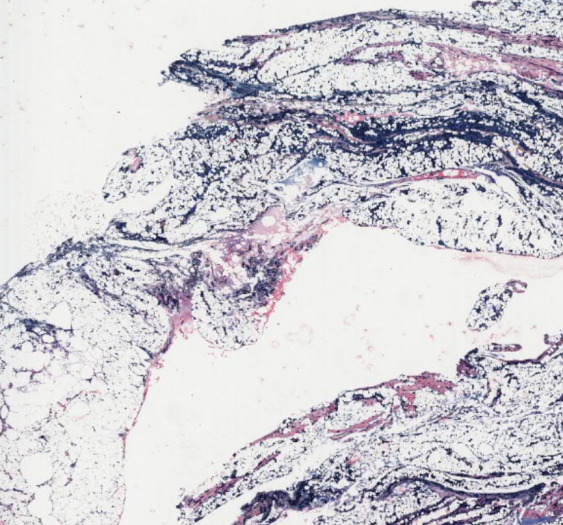

细胞和组织的适应与损伤

脂肪坏死